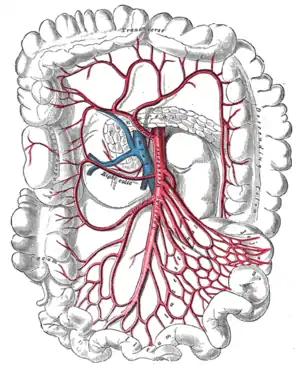

Blood supply comes from three arteries branching off the aorta: the coeliac artery, the superior mesenteric artery, and the inferior mesenteric artery.

Superior Mesenteric Artery

Supplies blood to the small intestine as well as the superior part of the colon. Notice the system of arching anastemoses that is a feature of the splanchnic arteries.